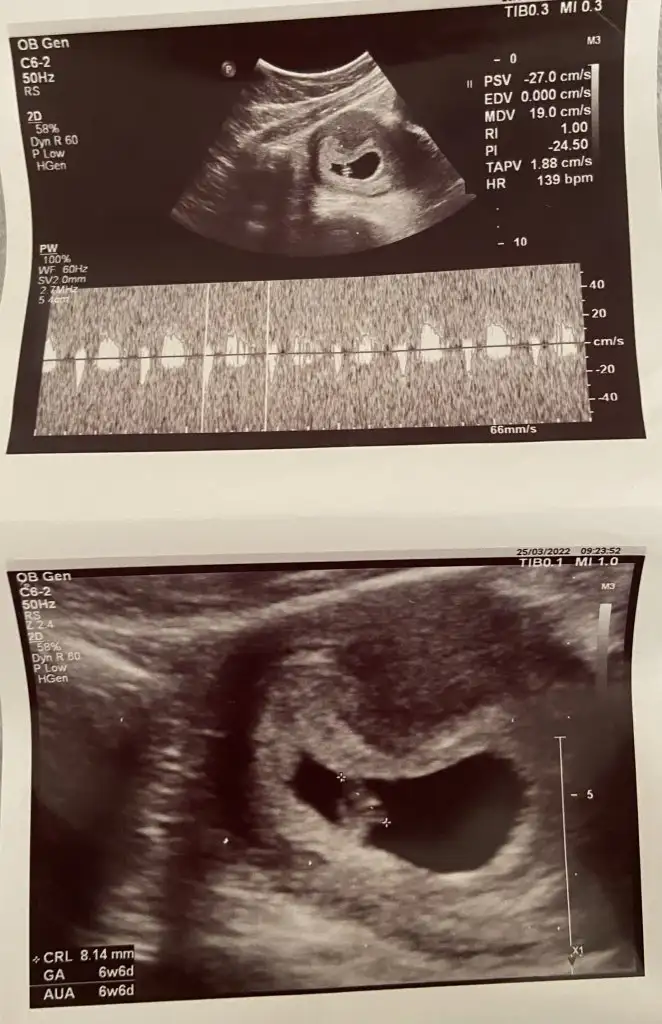

Merhaba ultrasona göre 6 hafta 6 günlük karından ultrason çekildi bana da tahminde bulunabilir misiniz?

• 1073AB50-F7B3-47FF-86D8-26C7B21604EF.webp

1073AB50-F7B3-47FF-86D8-26C7B21604EF.webp

46,1 KB · Görüntüleme: 246